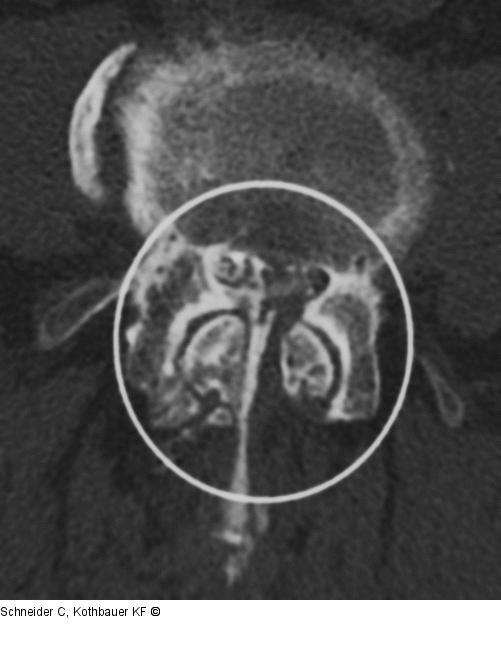

Abbildung 1: Facettensyndrom Myelographie-CT (axiales Knochenfenster): Typische degenerative Facettengelenksarthrose mit Sagittalstellung der Gelenke, Gelenksinkongruenz, spondylophytärem Anbau und konsekutiver Spinalkanalstenose. |

Myelographie-CT (axiales Knochenfenster): Typische degenerative Facettengelenksarthrose mit Sagittalstellung der Gelenke, Gelenksinkongruenz, spondylophytärem Anbau und konsekutiver Spinalkanalstenose. |